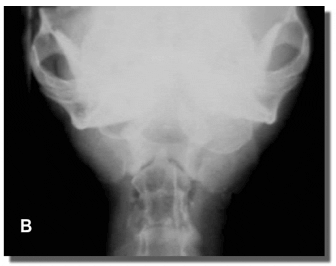

El diagnóstico de las patologías vestibulares periféricas requiere un examen detallado de la faringe y los oídos. La radiología de cráneo en distintas incidencias y la tomografía computada (TC) permiten la correcta evaluación de las ampollas timpánicas y de la porción petrosa del hueso temporal (Figura 8).

Figura 8: Rx de cráneo en incidencia L-L (A), y en incidencia D-V (B) Nótese el aumento de tamaño (expansión) y de la densidad de la ampolla timpánica izquierda. La imagen es altamente compatible con la presencia de pólipos.